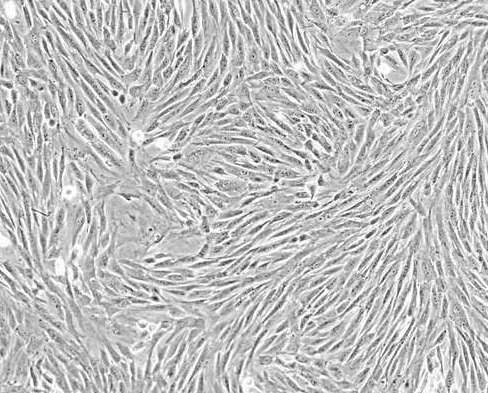

間充質干細胞療法

圖片17.png

間充質干細胞(MSC)是干細胞家族中重要成員,它們來源于發育早期的中胚層和外胚層。MSC在體內或體外特定的誘導條件下,可以分化為多種組織細胞,連續傳代培養和冷凍保存后仍具有多向分化的潛能,可用于衰老和病變引起的組織器官損傷修復。尤其是與免疫反應和再生修復相關的疾病的治療中具有極大的應用潛力。

間充質干細胞的免疫性抑制特性恰好能夠為自身免疫疾病的治療提供解決方案。例如,1型糖尿病、類風濕性關節炎、系統性紅斑狼瘡等。